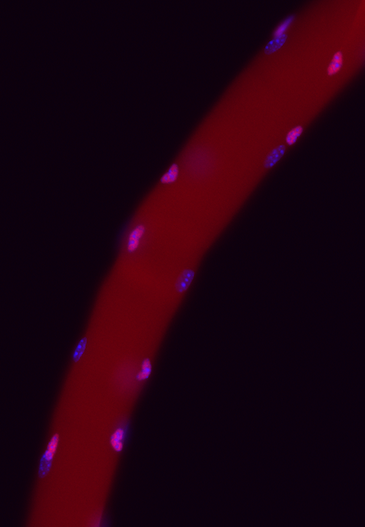

Skeletal muscles have remarkable regeneration potentials. The secrets are the stem cells that reside on myofibers. In healthy tissues, muscle stem cells largely remain in dormancy or a quiescent state. But they can respond to myofiber injury promptly, and orderly undergo the processes of proliferation, differentiation and fusion to repair injured muscles. Although working hard, muscle stem cells do not exhaust themselves and know precisely when to self-replicate & return to the quiescence. This self-renewal decision is essential for allowing them to regenerate tissues in the future. We therefore study the key signaling pathways that determine the fate choice of muscle stem cells.